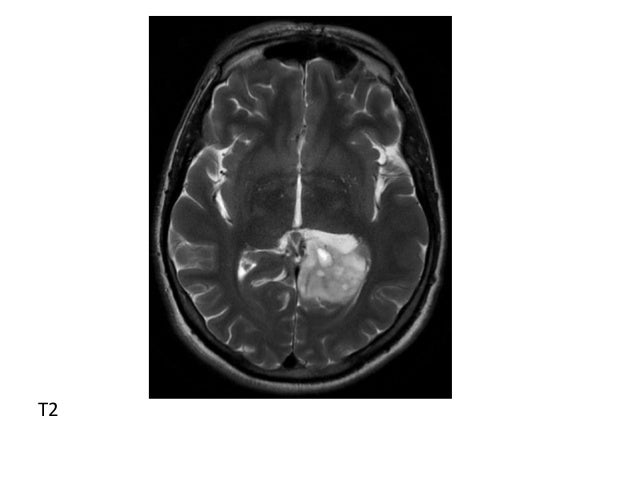

44+ Butterfly Brain Tumor Ct Scan UK. A butterfly glioma is most frequently a malignant glioma, but the butterfly description means that the tumor has crossed over the midline of the brain to involve both the right and left hemispheres. Central primary cns lymphomas start bilaterally in the centrifugal postcontrast ct scan showing a thalamic lymphoma (left image) that started to fungate centrifugally outward on follow up ct scan (middle.

Brain ct scans may be done with or without contrast. contrast refers to a substance taken by mouth or injected into an intravenous (iv) line that. This uses a strong magnetic field and radio waves to provide a detailed image of the brain. The tumor often appears symmetrical, like the wings of a butterfly. Doctors may also refer to a tumor based on the site from which the cells originated.